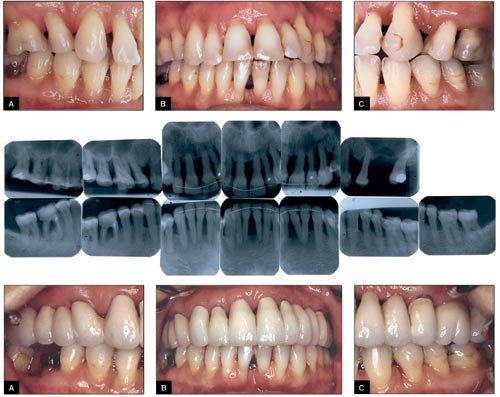

Fig. 5 – 7. Patientfall 2.

Fig. 5. (överst) A-C. Kliniska foton vid första undersökningstillfället.

Fig. 6. (midt). Apikalröntgen i anslutning till primärundersökningen (26 extraherades före röntgenundersökningen).

Fig. 7. (nederst) A-C. Kliniska foton efter icke-kirurgisk och kirurgisk behandling.

Fall 2 är en kvinna född 1958 som remitterats till specialistkliniken för parodontologi i Malmö för generell grav parodontit. Patienten är frisk och tar inga mediciner men är allergisk mot vissa födoämnen, damm och kvalster. Hon tål lokalanestesi och penicillin och röker cirka 10 cigaretter per dag sedan 20 år. Patienten har stor erfarenhet av tandvård. Hon upplever att problemet med parodontit uppstod efter en ortodontibehandling 1986 – 89. Hon har därefter fått behandling av parodontolog men valde själv att avstå från vidare stödbehandling.

Patienten saknar enstaka tänder och har ett postnormalt bett som är frontalt öppet. Både överkäks- och underkäksfronterna är fixerade med komposit och retentionsbåge.

Den primära parodontala undersökningen visar bland annat följande: andelen tandköttsfickor >5 millimeter är 27 procent, PLI = 13 procent och BOP = 31 procent.

Parodontal diagnos: Generell aggressiv parodontit med et complicatakaraktär.

Vid behandlingen samarbetar parodontolog, protetiker och ortodontist. Inledningsvis extraheras tänder med dålig prognos, det vill säga 17, 16, 23. Separation och extraktion görs av den distala roten på 46. Samtidigt genomförs hygienbehandling som består av sjukdomsinformation och upprepade instruktioner i munhygien. Därefter genomförs parodontalkirurgi vid kvarstående fördjupade tandköttsfickor som uppvisar patologi. Parodontalkirurgin består av både gingivektomi och modifierad Widman-lambå. För att retroklinera överkäksfronten aktiveras en facialslinga från 13 till 23 buccalt en månad efter att parodontalkirurgin genomförts och man uppnått god initial läkning. Den ortodontiska behandlingen genomförs på drygt tre månader. Därefter retineras tänderna med en semipermanent fullbro i överkäken, 18,17,16,15,14,13,12,11,21,22,23,24,25,26,27. Bron görs i Remanium (en kobolt-krom-legering) och porslin.

Efter avslutad parodontologisk, ortodontisk och protetisk behandling har andelen fördjupade tandköttsfickor >5 millimeter reducerats till 8 procent, PLI = 10 procent och BOP = 10 procent.

Tänderna i överkäken har en tveksam prognos, medan tänderna i underkäken bedöms ha en god prognos under förutsättning att patienten fortsätter med nuvarande munhygienrutiner och kommer på regelbundna stödbehandlingsbesök. Patienten är nu mermotiverad att försöka att sluta röka. Det skulle sannolikt förbättra prognosen.

I det här fallet är det viktigt att parodontiten behandlats innan den ortodontiska behandlingen påbörjas. En studie visar att en kombination av inflammation, ortodontiska krafter och ocklusalt trauma kommer att resultera i en mycket snabbare progression av vävnadsdestruktionen än vad enbart den inflammatoriska processen kan resultera i (9).